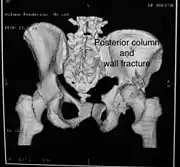

Posterior column and wall fracture as seen on 3D CT

Posterior column and wall fixed using screws and plates

Both column fracture showing floating weight bearing dome